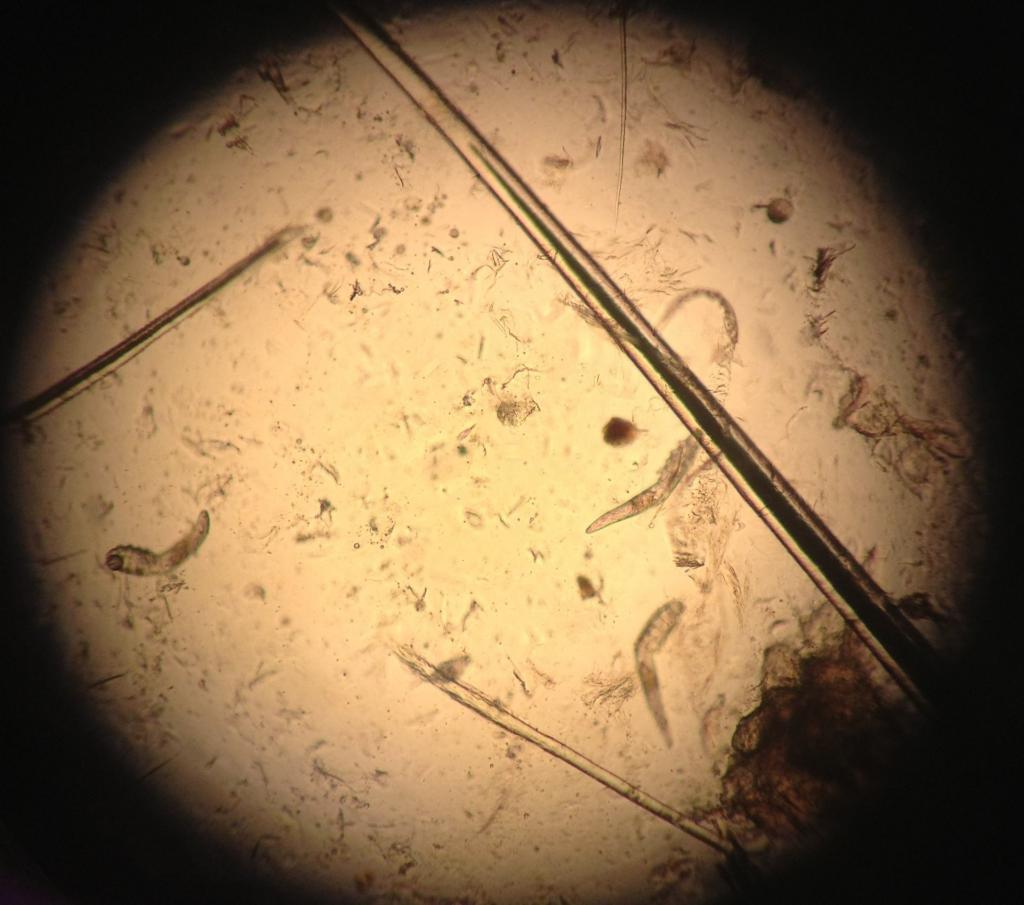

Так, например, выяснилось, что взрослый клещ достигает максимального размера до 0,4 мм. У него полупрозрачное вытянутое туловище и 8 лапок. Тело покрыто мелкими чешуйками, которые позволяют им цепляться за волосяной фолликул. Кроме того, у этого существа есть ротовой аппарат, с помощью которого ему удается поедать скапливающиеся в волосяных сумках частички сальных желез, клетки кожи и гормоны.

Яйца самки клещей откладывают внутри сальных желез или волосяного фолликула. Спустя 3-4 дня вылупляются личинки, еще через неделю они превращаются во взрослых особей. Период жизни клеща Demodex brevis — несколько недель. После гибели тело членистоногого разлагается внутри сальной железы или фолликула.

Анализ на клеща демодекс делается просто и безболезненно. Специалист берет соскоб кожи лица или волосяного покрова (брови, ресницы) и отправляет его на исследование в лабораторию. Далее проводится его изучение под микроскопом. Именно так можно увидеть полупрозрачных паразитов и результаты их жизнедеятельности.

Исключительно по внешним признакам определить наличие клеща практически невозможно. Поэтому пораженные участки следует изучить под микроскопом.

Затем врач-дерматолог проводит соскоб с кожи лица в нескольких местах. Соскоб рассматривается под микроскопом, анализ не занимает более 10 минут. Диагноз ставят при обнаружении на коже более 5 клещей на 1 см². Если клещей меньше, то ставят диагноз носительства.

Чтобы диагностировать демодекоз век после осмотра необходимо взять на анализ по 4 ресницы с каждого века и рассмотреть волосяную луковицу под микросокопом. Диагноз ставится в том случае, если при обследовании было выявлено более 4-5 паразитов.

Начиная с г. D.folliculorum не видны невооруженным глазом, вам нужно будет обратиться к врачу, чтобы поставить точный диагноз. Чтобы диагностировать этих клещей, ваш врач соскоблит небольшой образец фолликулярной ткани и масла с вашего лица. Биопсия кожи, показанная под микроскопом, может определить наличие этих клещей на лице.

Клещи слишком малы, чтобы их можно было увидеть невооруженным глазом, поэтому врач обычно делает биопсию кожи. Для этого нужно взять образец кожи и изучить его под микроскопом.

Важно определить количество клещей, обитающих на коже. Небольшое количество клещей вряд ли станет причиной проблем с кожей человека.